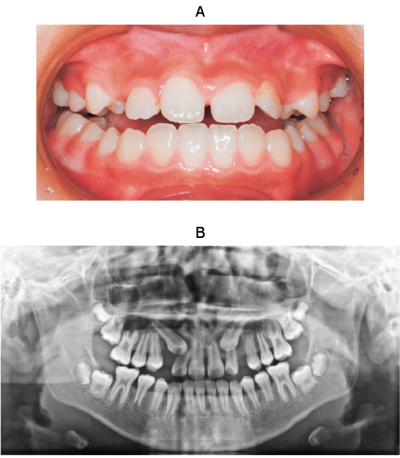

11 歳の女児。上顎両側犬歯部の空隙を主訴として来院した。前歯部の被蓋関係は正常である。初診時の口腔内写真、エックス線画像及び歯科用コーンビーム CTを別に示す。まず行うべき対応はどれか。1つ選べ。

a. 経過観察

b. 上顎中切歯間の空隙閉鎖

c. 上顎両側犬歯の開窓牽引

d. 上顎両側側切歯の歯内療法

e. 上顎両側第一小臼歯の近心移動